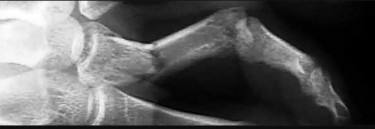

- الأشعة السينية (X-rays): هي الخطوة الأولى في تقييم الكسور، الخلوع، وتغيرات التهاب المفاصل. تساعد في تحديد مدى تدهور العظام والمسافات المفصلية. على سبيل المثال، تُظهر صور الأشعة السينية كسور السلاميات

أو كسور قاعدة العظم المشطي الخامس

، بالإضافة إلى علامات مثل "الدمعة الشعاعية" (Radiographic Teardrop) في الرسغ التي تمثل الزاوية الزندية الراحية الحرجة للكعبرة البعيدة

. - الأشعة المقطعية (CT Scan): توفر صوراً تفصيلية ثلاثية الأبعاد للعظام، وهي مفيدة جداً لتقييم الكسور المعقدة، مثل كسور العظم الخطافي (Hamate Hook Fracture) التي قد لا تظهر في الأشعة السينية العادية